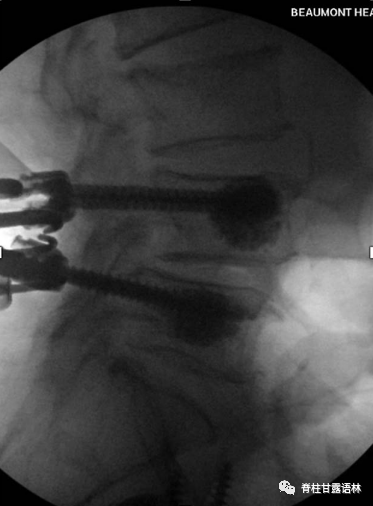

图4 侧孔骨水泥螺钉的使用